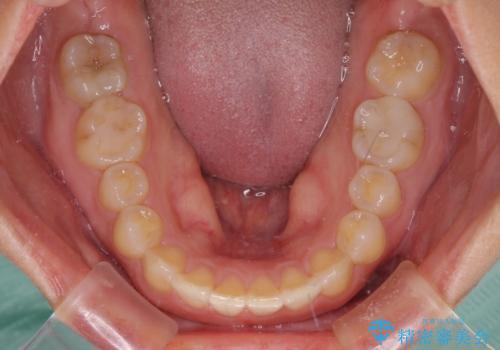

- 前歯の空隙と矮小歯を気にして来院された患者様です。

上下の歯列不正はインビザラインにより整えることとしました。

矯正治療の後に、前歯1歯と奥歯をオールセラミックにて治療することとしました。

矯正治療により矮小歯前後にスペースを作りながら歯列を整え、セラミッククラウン装着後に最終的に歯列と咬合を仕上げました。